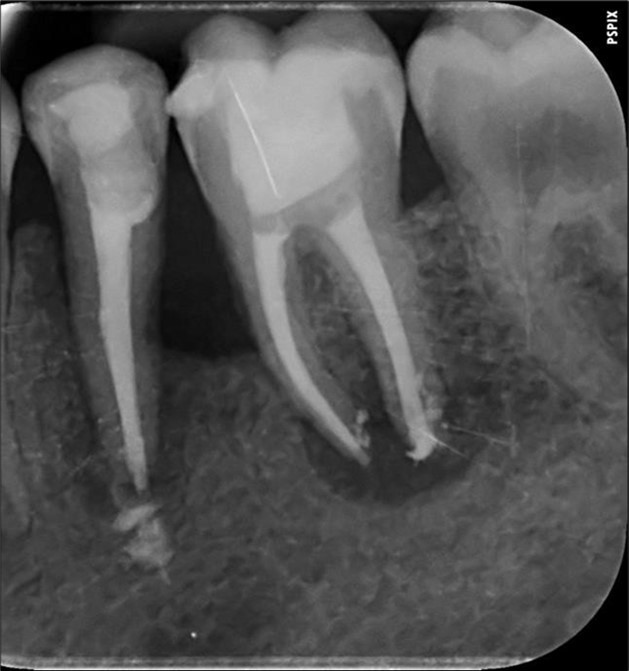

3. Endodontic root canal treatment and retreatment were performed on teeth 14, 15, 16, 25, 26, 35, 36, and 46 using a K manual file 10/30/40/50/60/70 (Dentsply-Maillefer). Hyflex Edm (Coltene) 25/06 was used for the preparation of the canals, which were irrigated with 3% sodium hypochlorite and 17% ethylenediaminetetraacetic acid. Gutta-percha were calibrated to the diameter of the root apex constriction and obturation was conducted using Endosequence Bc Sealer (Brasseler) 15.

Complete healing of periapical lesions and treatment of teeth 26 and 16 with advanced endo-perio lesions posed challenges due to the patient’s delayed supplementation. In this case, surgical endodontic procedures and the extraction of teeth with advanced endo-perio lesions were considered risky because of the underlying metabolic healing impairment. Figure 3

Figure 3.6. 7, 8, 9, and 10 showing postoperative periapical radiographs of these endodontic treatments.

6. 7, 8, 9, and 10 showing postoperative periapical radiographs of these endodontic treatments.